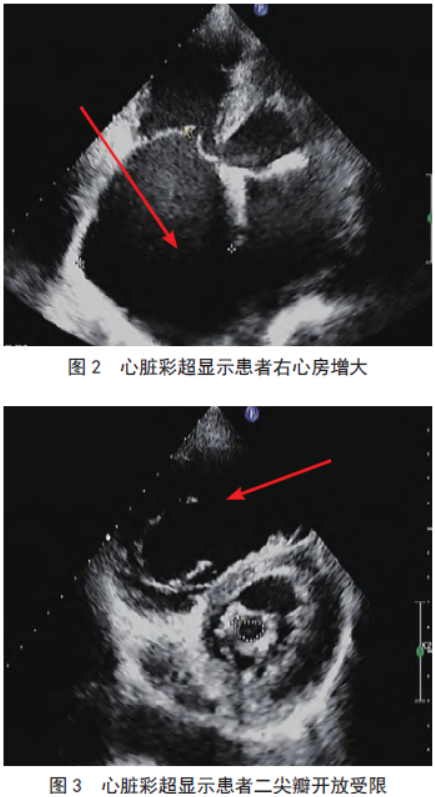

心脏彩超(图2-4)示:双房扩大、主动脉窦部增宽、升主动脉扩张、肺动脉扩张、主动脉瓣退行性改变伴轻度反流、二尖瓣狭窄

伴二尖瓣重度反流(二尖瓣最大开放径12 mm,解剖面积0.98 cm2)、三尖瓣重度反流、肺动脉高压、左房压增高。未吸氧时测动脉血气:pH 7.38,血二氧化碳分压54 mmHg,血氧分压32 mmHg,碱剩余

6.8 mmol/L;经鼻吸氧(氧浓度37%)2 h 后所测的动脉血气:pH7.48,血二氧化碳分压39 mmHg,血氧分压108 mmHg,碱剩余5.5 mmol/L。评估代谢当量为4,心功能Ⅲ级,美国麻醉医师协会分级Ⅲ级。